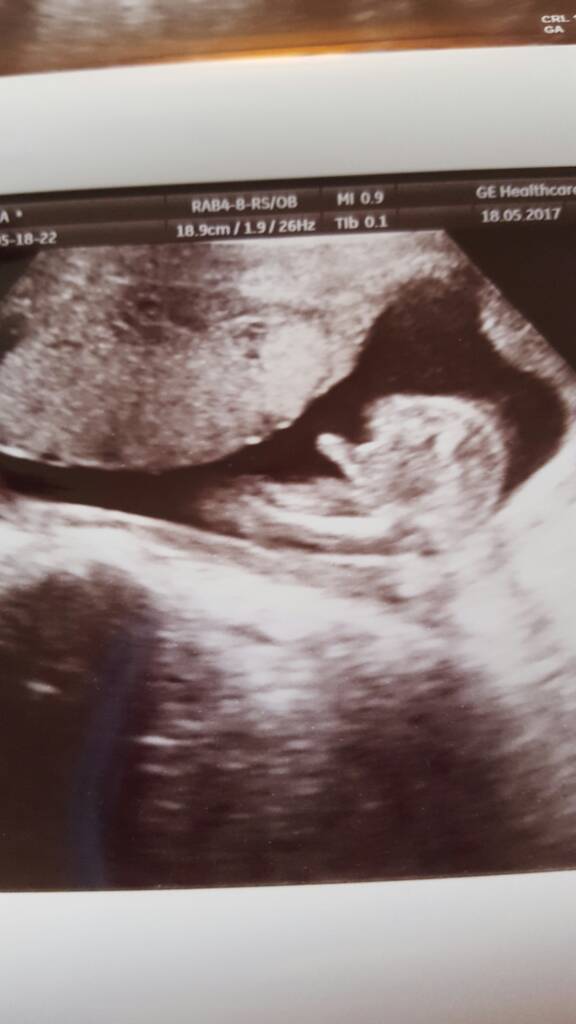

1495194458-aaaaaa.jpeg

Trochę zmienił położenie ale jest mocno wtulony w łożysko i ciężko było zrobić ładne zdjęcia ale coś się udało.

1495194514-aaaaaa.jpeg

1495194530-aaaaaa.jpeg

Najlepsze jest to, że według Polskich pomiarów jest mniejszy ale w normie więc się nie martwię.

1495194633-aaaaaa.jpeg